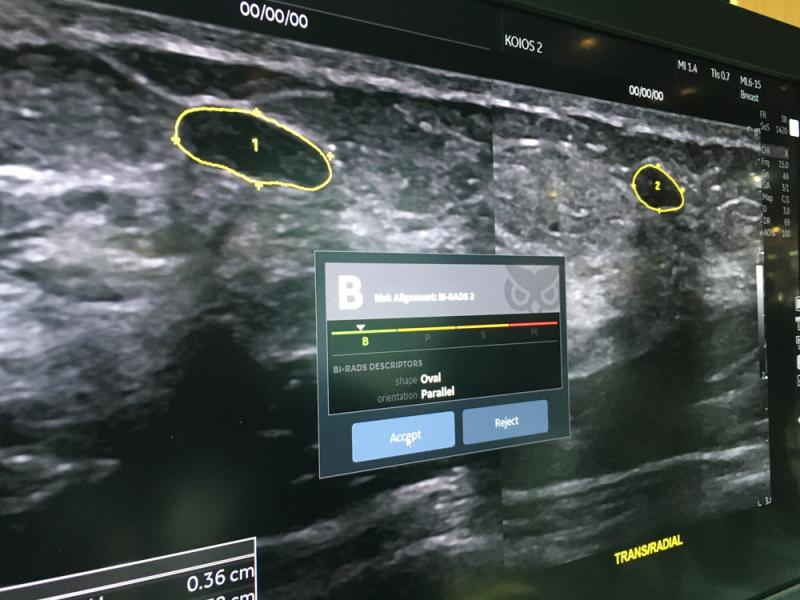

Here are images of some of the newest new medical imaging technologies displayed on the expo floor at the Radiological Society of North America (RSNA) 2019 meeting. Use the slider images below to see the photos.